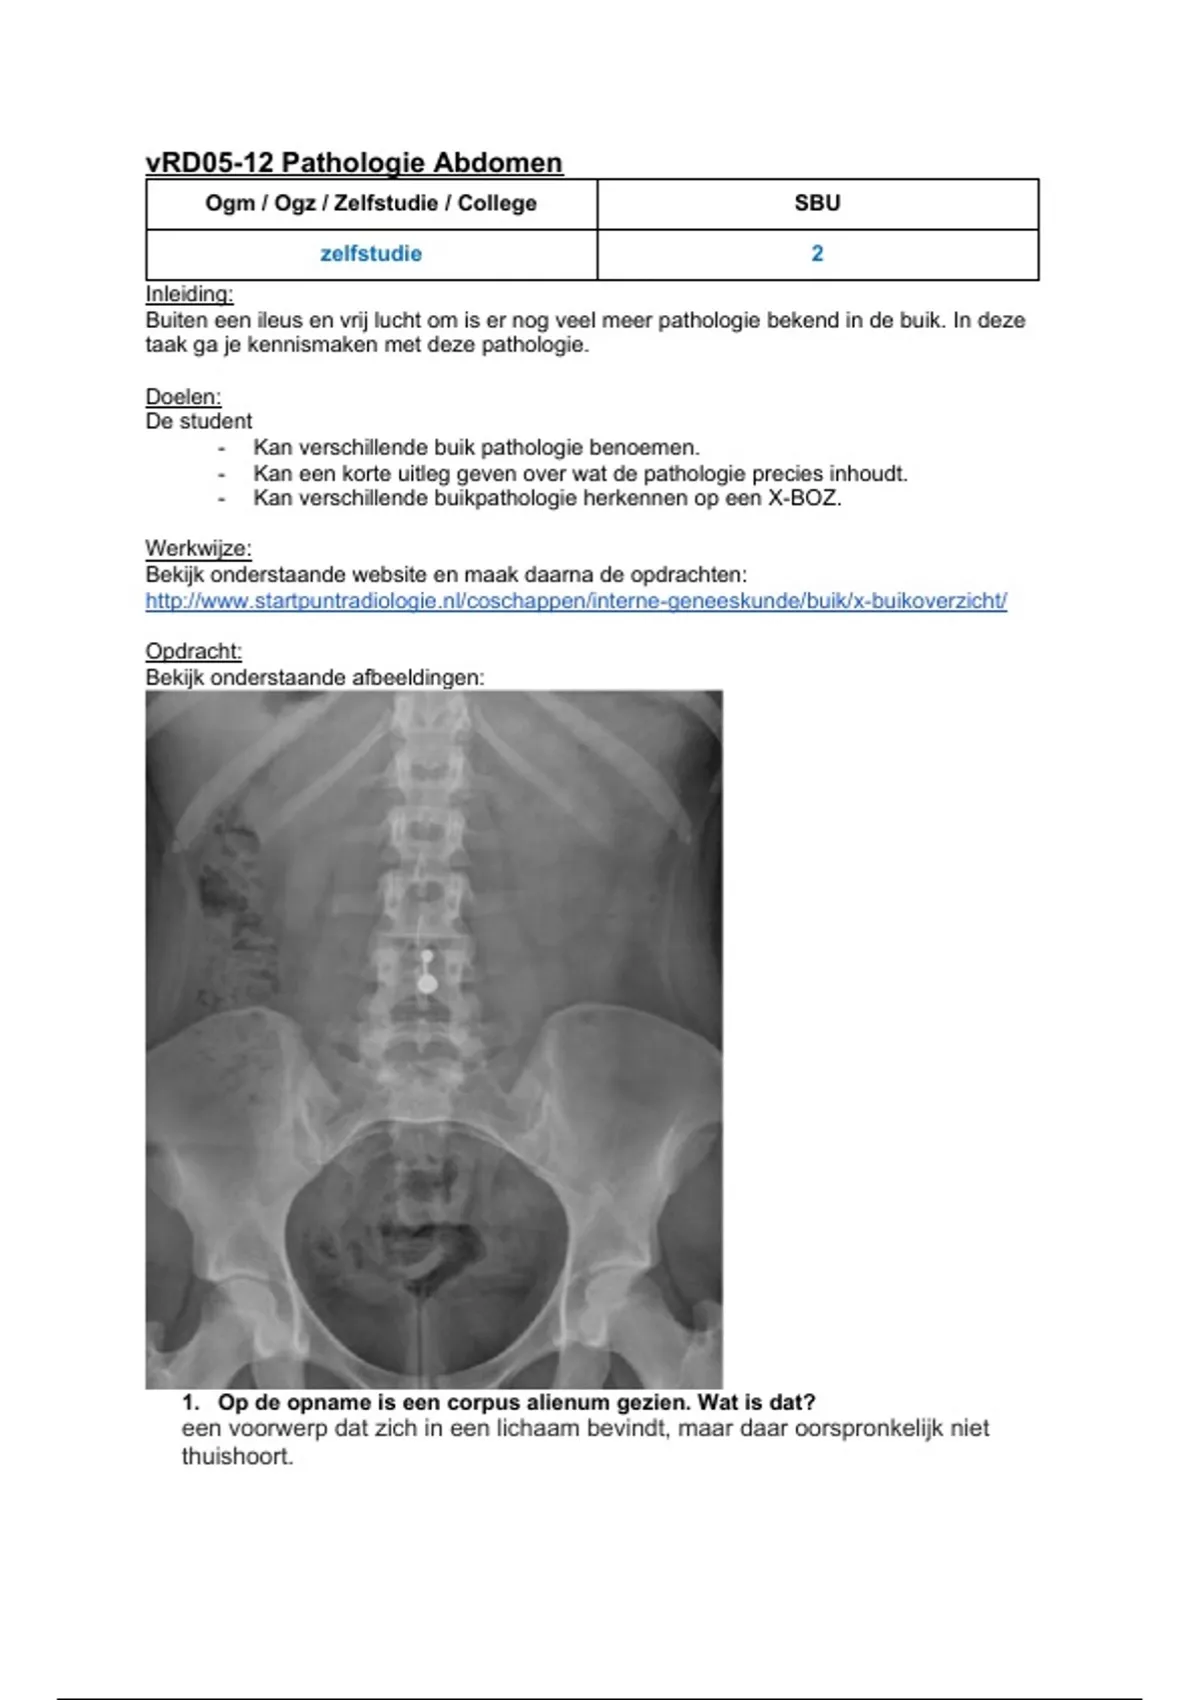

Bekijk onderstaande afbeeldingen:

1. Op de opname is een corpus alienum gezien. Wat is dat?

een voorwerp dat zich in een lichaam bevindt, maar daar oorspronkelijk niet

thuishoort.

, 2. Wat is de Latijnse naam voor de pathologie die zichtbaar is op bovenstaande

opname?

nierstenen

3. In welke anatomische structuur is de pathologie zichtbaar? Kan je bedenken

wat voor klachten deze patiënt kan ervaren?

ureter (urineleider)